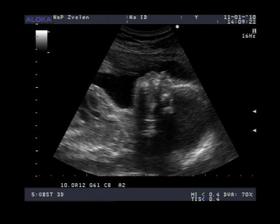

- 10.12.09 - morfologicke utz. ..... podla p. doktora je malicke v poriadku, vazime 300g 🙂